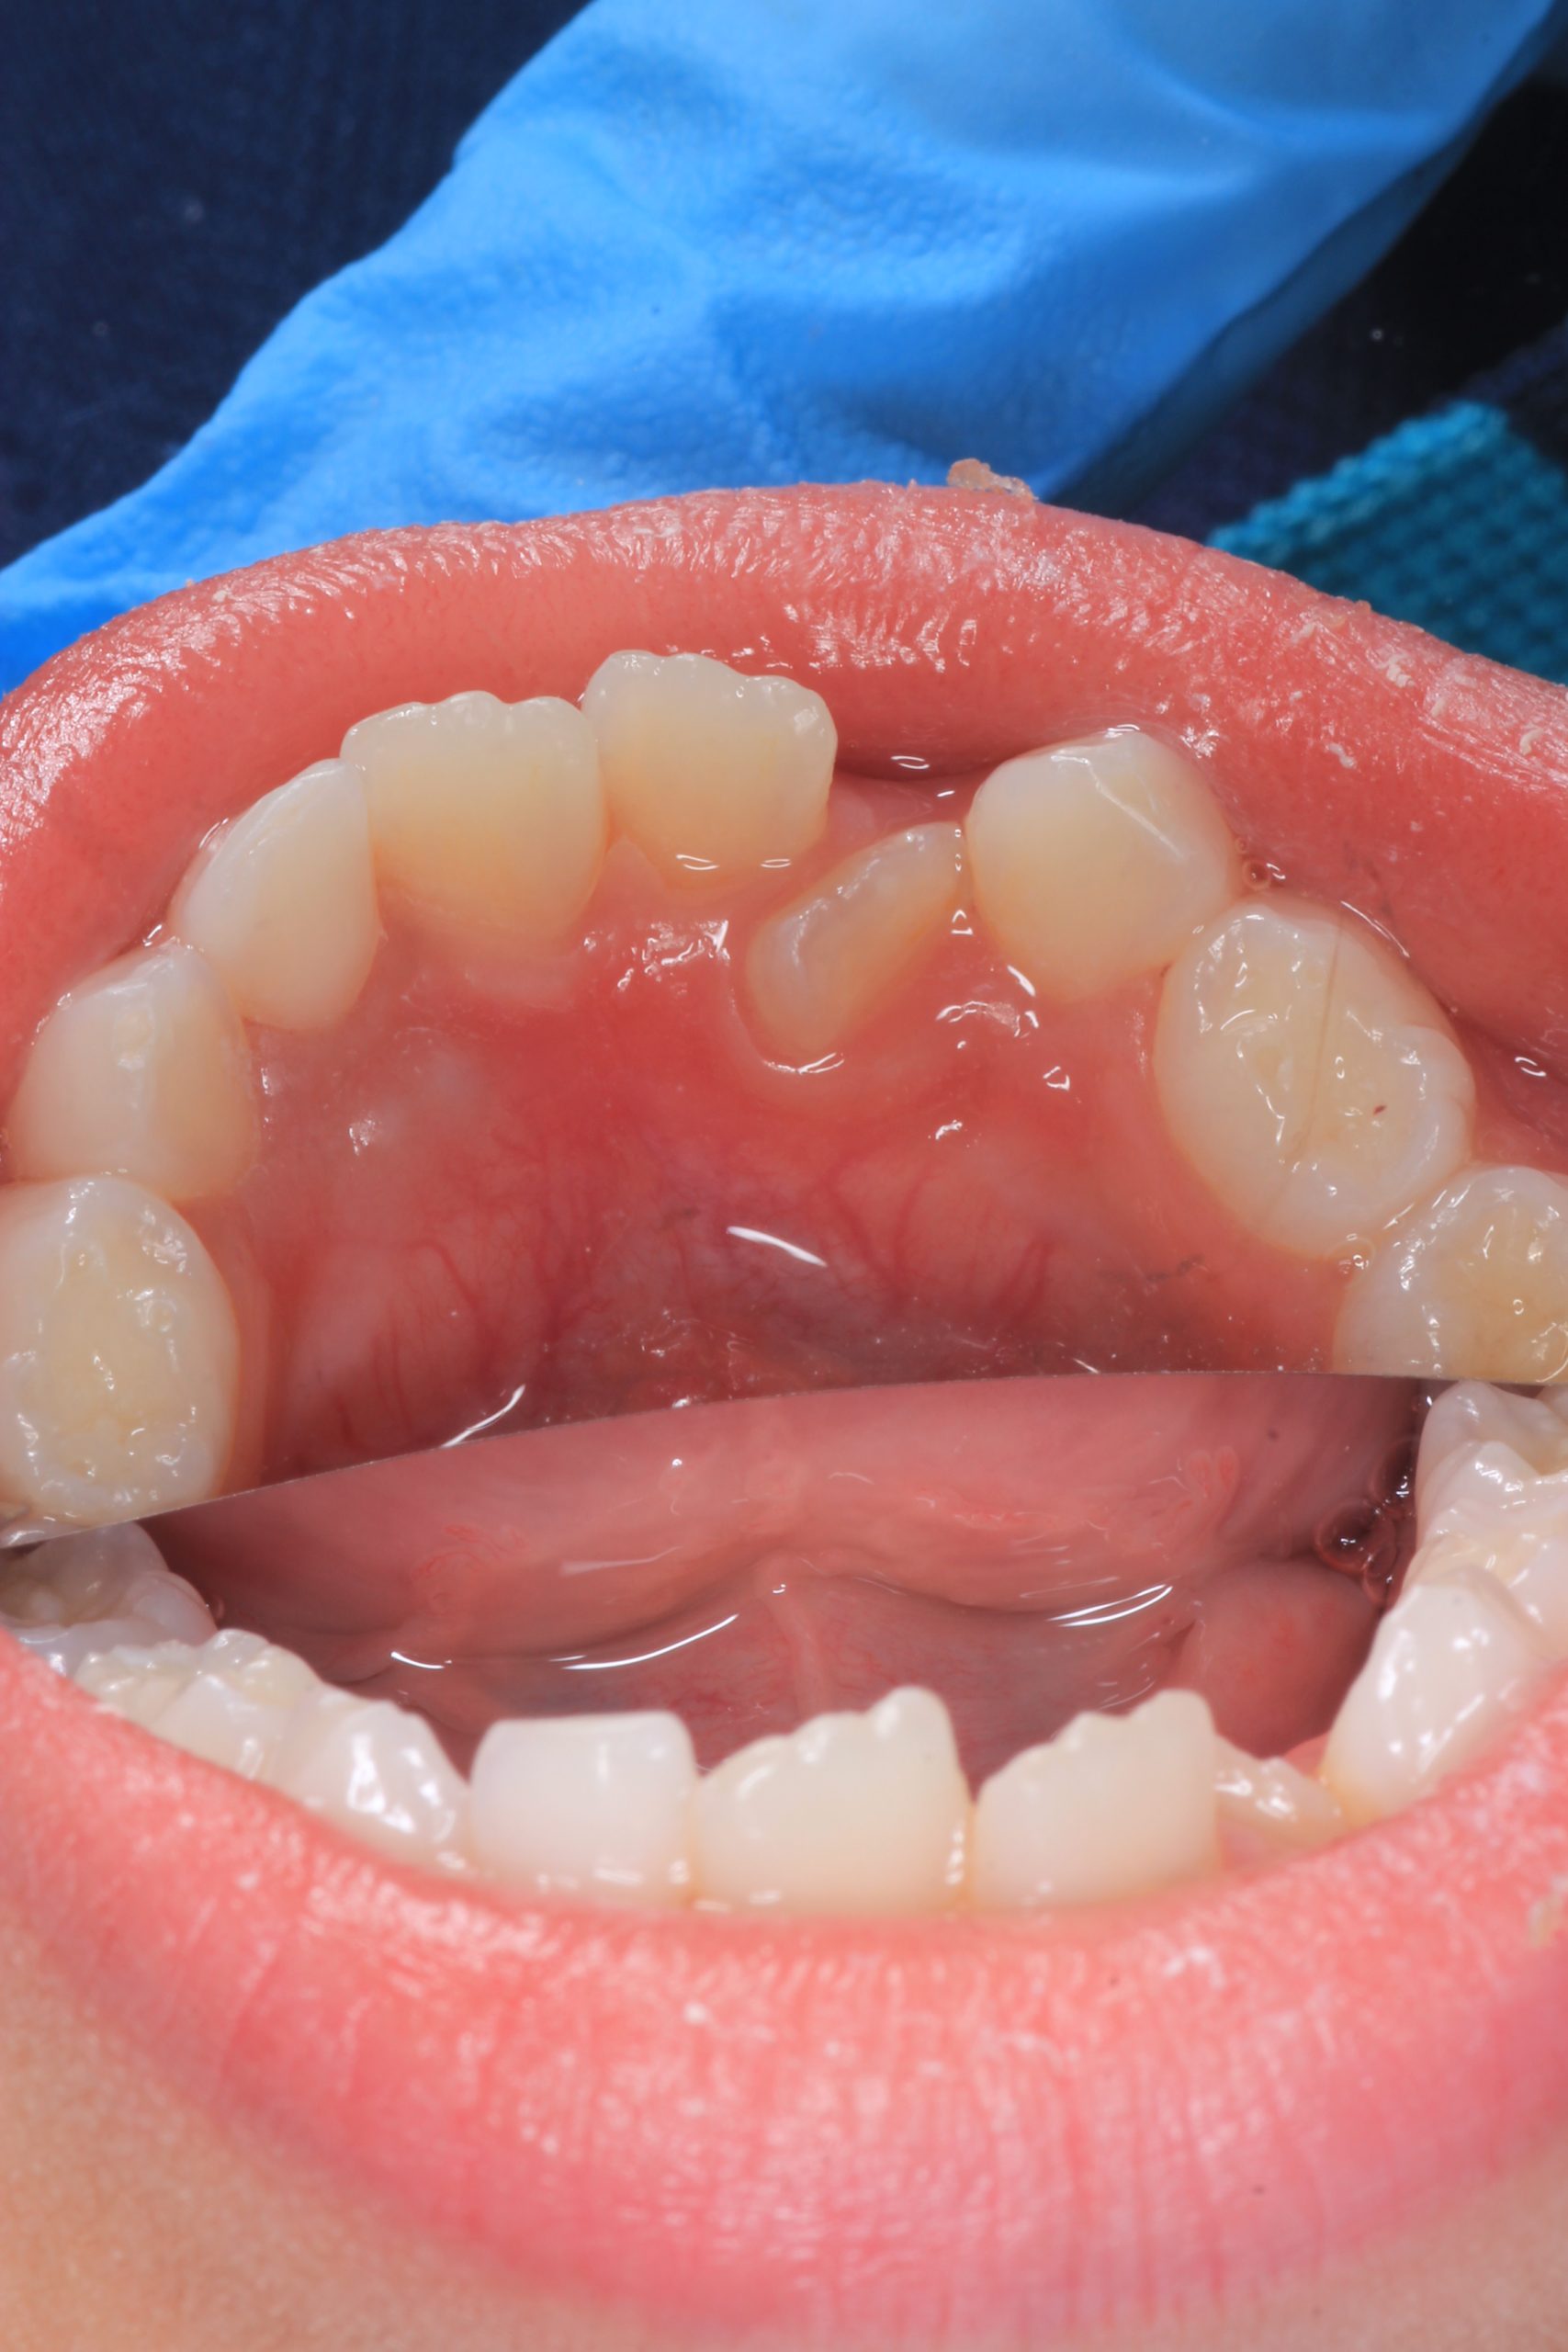

We examine the condition of teeth, gums, and bite. - Plaque Disclosure with Special Indicators

Areas that weren’t cleaned well appear purple. The darker the shade, the older the plaque. This helps both kids and parents understand where brushing needs to improve. - Brushing Training & Home Care Tools Selection